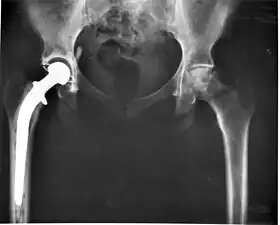

Medical implants

An implant is a kind of medical device made to replace and act as a missing biological structure (as compared with a transplant, which indicates transplanted biomedical tissue). The surface of implants that contact the body might be made of a biomedical material such as titanium, silicone or apatite depending on what is the most functional. In some cases, implants contain electronics, e.g. artificial pacemakers and cochlear implants. Some implants are bioactive, such as subcutaneous drug delivery devices in the form of implantable pills or drug-eluting stents.

Some examples include pacemakers, infusion pumps, the heart-lung machine, dialysis machines, artificial organs, implants, artificial limbs, corrective lenses, cochlear implants, ocular prosthetics, facial prosthetics, somato prosthetics, and dental implants.

- Class III devices generally require premarket approval (PMA) or premarket notification (510k), a scientific review to ensure the device's safety and effectiveness, in addition to the general controls of Class I. Examples include replacement heart valves, hip and knee joint implants, silicone gel-filled breast implants, implanted cerebellar stimulators, implantable pacemaker pulse generators and endosseous (intra-bone) implants.